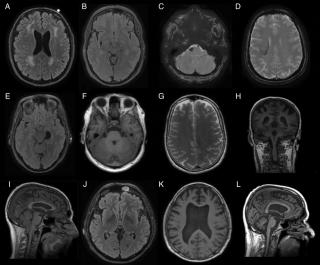

Липома головного мозга на МРТ достаточно четко визуализируется на любимой модели томографа. Диагностировать ее можно при МРТ головного мозга даже без применения контраста, поскольку МР сигнал от жирового образования очень специфичный, дифференцировать липому от других видов опухолей тоже не составит труда.

МРТ здорового головного мозга липома на МРТ головного мозга